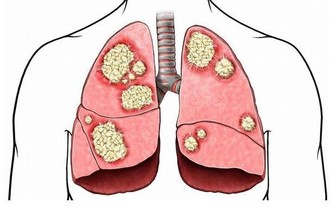

②惡性腫瘤淋巴結轉移,已經出現癌細胞轉移的淋巴結,質地比較硬,表面會有凹凸不平的樣子,還會和皮膚發生粘連,一般沒有疼痛感;